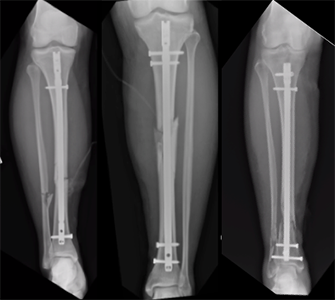

Hutchinson’s injury required immediate surgery, a typical approach for treating more severe fractures, especially if the bone is displaced or if there’s considerable damage to the surrounding muscles and tissues. This procedure often involves inserting metal rods, plates, or screws to realign and stabilize the bone, allowing for proper healing. After surgery, he will likely need a period of immobilization, where the leg is kept in place to facilitate bone regrowth and prevent further injury.

Once the initial healing is underway, Hutchinson will enter a rehabilitation phase that includes physical therapy to help restore strength, flexibility, and coordination in the injured leg. Given the nature of the fracture, recovery can take anywhere from four to six months, or possibly longer. For athletes like Hutchinson, who rely on peak physical condition, this process must be approached carefully to avoid complications.